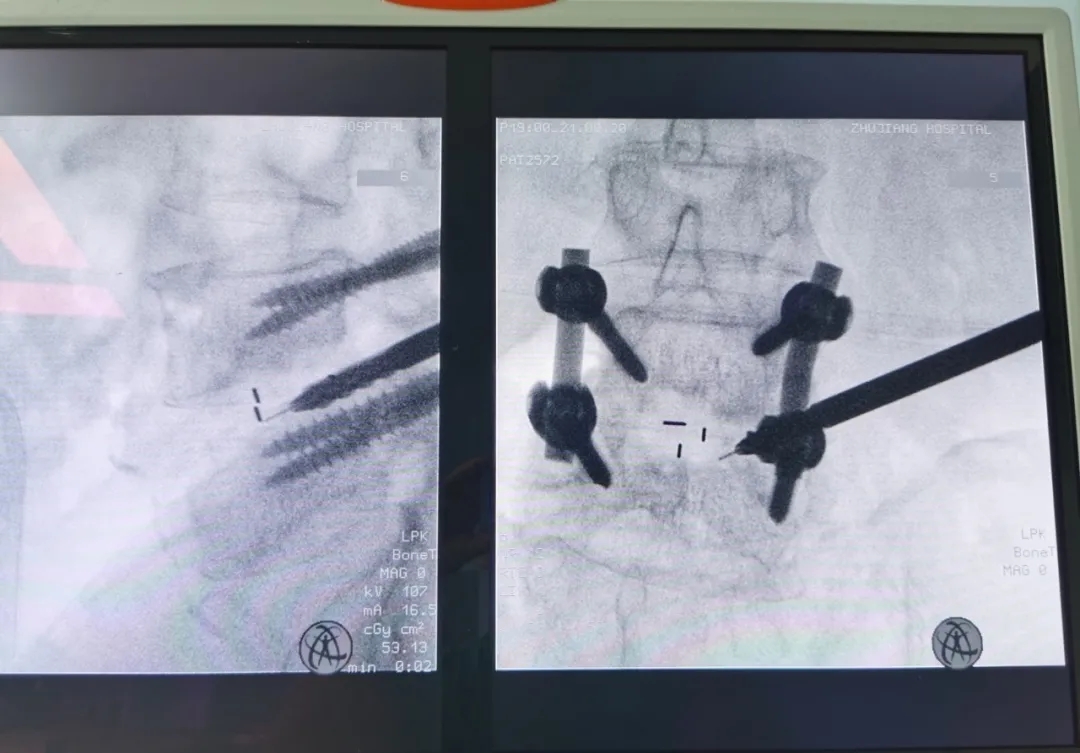

影像资料:

▲孔镜工作通道直达病灶